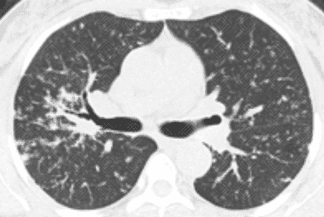

Descrição das figuras 1, 2, 3, 4 e 5: Tomografia computadorizada do tórax com cortes axiais evidenciando pequenos nódulos distribuídos principalmente ao longo dos brônquios e vasos pulmonares (setas vermelhas). Nos cortes coronal e sagital observa-se o predomínio das anormalidades descritas nas regiões superiores e médias, de localização mais central.

• As alterações pulmonares predominam nas regiões centrais e lobos superiores, sendo geralmente bilaterais e simétricas. Predominam os pequenos nódulos sólidos com distribuição perilinfática, ou seja, ao longo dos brônquios, septos interlobulares, vasos pulmonares e regiões subpleurais. Lesões nodulares escavadas e derrame pleural são raros na doença;